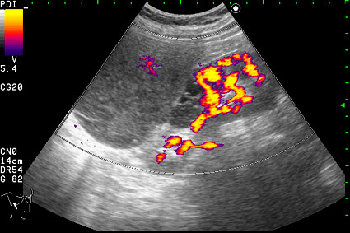

- Образование в режиме энергетического доплера.

Почечно-клеточный рак правой почки, кистозная форма.

Но только по густому содержимому кистозного компонента. Стенка тонкая, кровоток не прокрашивается (единичный мелкий срез сосуда в центре образования больше похож на артефакт, а м.б. им и является).

Если бы в этом случае и содержимое было бы более "жидким", вероятность постановки правильного диагноза была бы минимальной.